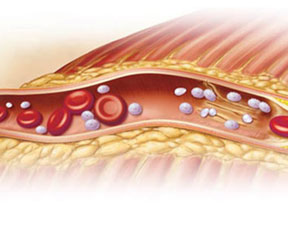

Eric T. Olson Illustration & Design

Eric T. Olson is an accomplished medical illustrator with over a decade of experience creating professional medical illustrations, graphics, and animations for major companies with expertise ranging from patient education to pharmaceutical training. His client list includes such names as Medtronic, Krames Patient Education, Boston Scientific, Novartis, and WebMD.

Eric is well-versed in the use of technology to ensure that the medical imagery he creates is appropriate to fit the needs of the viewer. By combining this technology with fundamental illustration skills, he delivers effective imagery that is equally informative, accurate, and visually appealing.